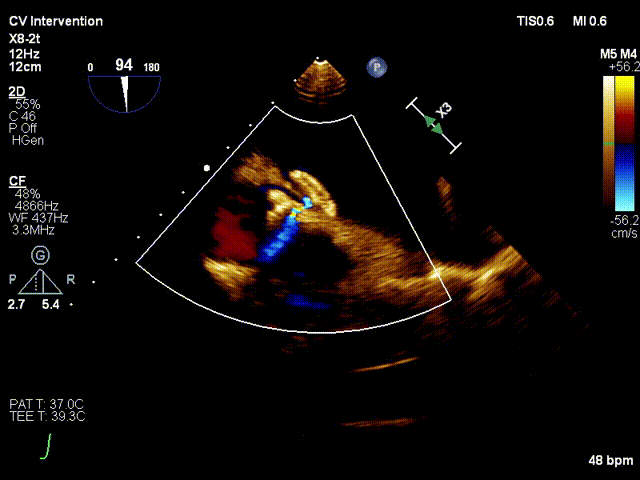

术中分流器形态稳定

食道超声可见左向右分流束